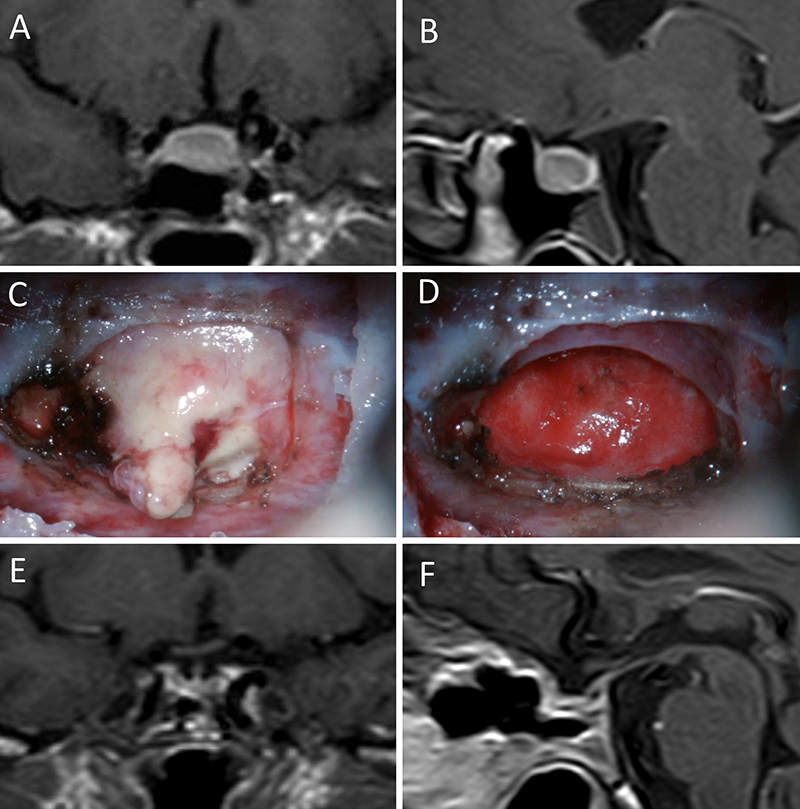

Figura 11: Microadenoma en una mujer de 36 años con Enfermedad de Cushing. Con remisión bioquímica tras la cirugía. A-B: RM preoperatoria; C-D: intraoperatorio; E-F: RM postoperatoria.

Figura 12: Microadenoma en una mujer de 26 años con Enfermedad de Cushing. Con remisión bioquímica tras la cirugía. A-B: RM preoperatoria; C-D: intraoperatorio; E-F: RM postoperatoria.